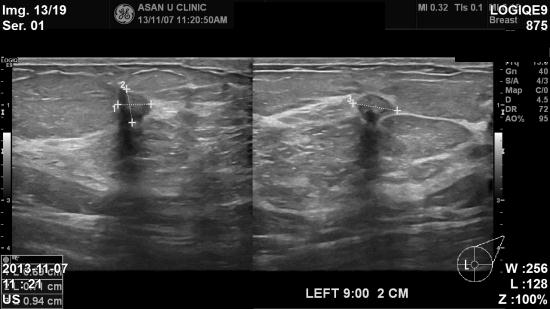

초음파검사결과 좌측유방에 새로운 종양이 생겨났는데

모양이 불분명하여

조직검사시행결과 침윤성 유방암으로

진단되셨습니다

.